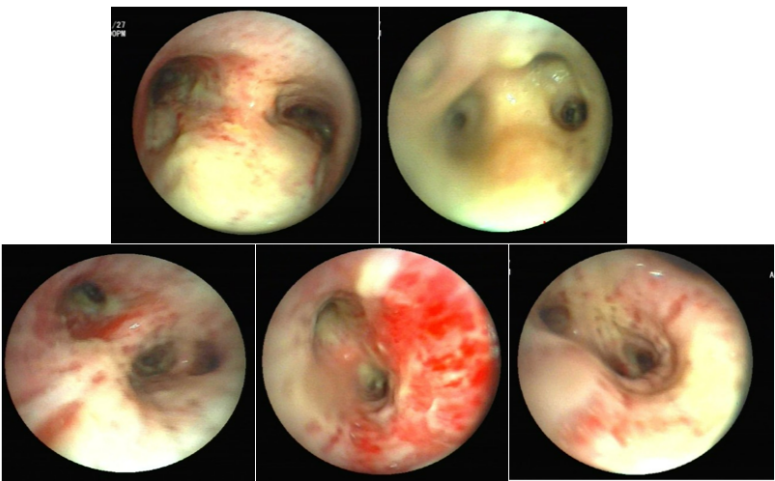

IAPA在发展过程中,较早可出现咳嗽、咳痰,进而出现呼吸困难、呼吸衰竭、缺氧性ARDS,进展迅速,即使气管插管、建立人工气道,患者也常出现气道峰压逐渐升高、潮气量逐渐下降,常因呼吸衰竭而无法挽救。但因其临床表现不特异,导致早期识别存在一定困难。(1)气管-支气管侵袭征象:沿支气管分布的结节及斑片影。对于没有基础疾病的重症流感病毒性肺炎患者,粒细胞数量正常,在曲霉感染后肺组织内会出现白细胞介导的强烈的炎症反应,导致渗出性支气管炎、支气管或肺泡受损及出血坏死,但直接侵袭血管的曲霉丝较少且主要以非增殖状态存在,因此多出现弥漫全肺的非特异性气道受侵型表现,而血管受侵型表现少见。如下图所示,第1天,支气管壁似乎有轻度增厚。病情进展至第4天,支气管壁明显增厚。随后迅速发展为支气管周围炎,并沿支气管侵袭、播散。图源:Respirol Case Rep, 2016, 4(1):32-34.注:双下肺实变,沿支气管血管束分布的实变、空洞,斑片状渗出影。注:支气管壁增厚、树芽征和沿着支气管血管束分布的实变。(2)对于免疫抑制宿主,可出现典型的曲霉感染影像学表现,例如实变与空洞伴晕征、空洞内有丝状结构及悬浮结节。注: A图见多叶肺炎和严重的小叶中心性、节旁性肺气肿; B图见右肺中叶空洞性浸润, 右肺下叶致密实变。图源:Chest, 2021, 160(2):e181-e184.注:A图可见实变、空洞,空洞内见丝状结构及悬浮结节;B图可见空洞、空气新月征。IAPA一种特殊的类型——侵袭性气管支气管炎,在支气管镜直视下可见气管和/或支气管溃疡、斑块或结节、假膜,是其典型表现。图源:国际呼吸杂志, 2023, 43(4):448-453.肺活检组织、气道斑块、假膜或溃疡的活检/刷检标本中发现真菌菌丝等特征性病理表现,可作为确诊标准。此外,在痰、支气管抽吸物、支气管肺泡灌洗液(BALF)中找到曲霉菌丝也可作为临床诊断标准。图源:Lancet Respir Med, 2018, 6(10):782-792.注:支气管活检组织病理显示有坏死物质和真菌成分,菌丝呈分枝状。图源:Chest, 2021, 160(2):e181-e184.图源:Tuberc Respir Dis (Seoul), 2014, 77(3):141-144.半乳甘露聚糖(galactomannan,GM)是曲霉特有的细胞壁多糖成分。菌丝生长时,半乳甘露聚糖是最早释放的抗原,是早期检测曲霉感染的经典方法。主要包括血清GM试验和BALF GM试验。血清GM试验在非粒细胞缺乏患者敏感性较低,仅为50%左右;ICU IPA患者的血清GM试验敏感性仅为30%~50%。在IAPA患者中,当以0.5作为GM试验阳性阈值时,诊断率仅20%。对于非中性粒细胞减少患者,BALF GM试验比血清GM试验具有更高的IPA诊断效率。EORTC/MSG标准采用1.0作为单份BALF阳性阈值的标准,当同时联合血浆/血清GM试验阳性时,BALF标本阈值可下调至0.8。我国学者研究发现,当截断值从0.5增加到0.717时,BALF GM试验可以显著降低假阳性率。无论是2016年美国传染病学会(IDSA)发表的《曲霉病诊断和管理实践指南》,还是2017年欧洲临床微生物学和感染病学会(ESCMID)/欧洲医学真菌学联盟(ECMM)/欧洲呼吸学会(ERS)联合发表的《曲霉病的诊断和管理指南》,都提及血清曲霉特异性IgG抗体在慢性肺曲霉病中有最高的检测阳性率。但2023年Clin Microbiol Infect杂志发表的一篇文章显示,IPA组的曲霉IgG抗体水平明显高于非IPA组。采样时间为发病后1~3个月内亚组显著高于采样时间为发病后<1个月亚组,影像学出现肺部空洞性病变亚组显著高于非肺部空洞性病变亚组。经过对比发现,曲霉IgG抗体的特异性和阳性预测值显著低于BALF GM。PCR的优势在于不仅能检测出曲霉的属和种,还可通过识别CYP51A基因突变来判断是否存在三唑类耐药可能。标本选择顺序:BALF>血浆>血清,但已进行了抗真菌治疗患者的血样本PCR阳性预测值可从62%降至5%。单份PCR阴性结果可极大程度地排除IPA可能。PCR可能更适合用于可疑IAPA患者在拟行抗真菌治疗前的筛查以及治疗过程中的实时监测。mNGS优势在于覆盖能力广, 时效性好, 不受先前使用抗菌药物的影响, 并可提供病原鉴定分型、耐药基因及毒力因子分析。但其检测成本较高, 结果需要临床医生进行解读和判断, 标本选择以BALF为最佳。